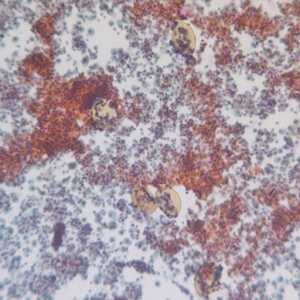

April - 2008 - Case #225

An 8-year-old child was taken to a hospital with fever, hepatomegaly, and persistent cough. The parents told the physician that the child commonly eats dirt, even though they have tried to discourage the habit.